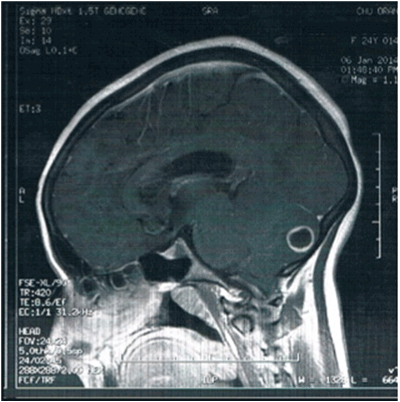

Figure 1: Brain magnetic resonance imaging. A hypointense signalmass in the left hemisphere of the cerebellum corresponding to asous-cortical postero-paramedian abscess measuring 13 mm showing unique ringenhancing lesion, surrounded by edema.

Brain magnetic resonance imaging (MRI) confirmed a hypointensesignal mass in the left hemisphere of the cerebellum (Figure 1). Cervical spine MRI revealed a normal spinal column with herniation of the cerebellar tonsil.